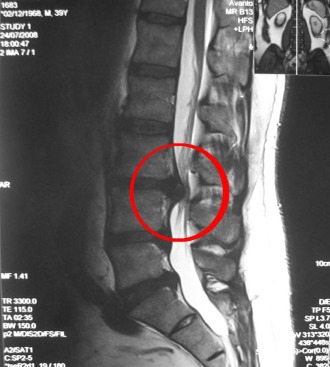

Межпозвоночные диски могут подвергаться износу и разрушению из-за заболеваний костной системы, а также могут рваться под воздействием чрезмерных нагрузок. При разрыве диска в позвоночный канал выходит полужидкое ядро диска, что приводит к образованию межпозвоночной грыжи.

Разрыв межпозвоночного диска может сжимать корешки спинномозговых нервов, что и вызывает радикулит. Кроме того, возникновение этого синдрома может быть связано с остеофитами – костными наростами на позвонках, которые образуются при уменьшении высоты межпозвоночных дисков.

Врачи отмечают, что радикулит поясничного отдела позвоночника часто проявляется резкой болью в нижней части спины, которая может иррадиировать в ноги. Симптомы могут включать онемение, покалывание и слабость в конечностях. Основными причинами радикулита являются остеохондроз, межпозвоночные грыжи и травмы. Для диагностики врачи рекомендуют проводить магнитно-резонансную томографию или компьютерную томографию.

Далее пациента направляют на рентгенографию – результаты этого исследования помогут определить точное местоположение повреждения позвоночника и выявить возможные места сжатия спинномозговых нервов.

Если данных рентгена недостаточно для точной диагностики, пациента могут направить на компьютерную или магнитно-резонансную томографию.